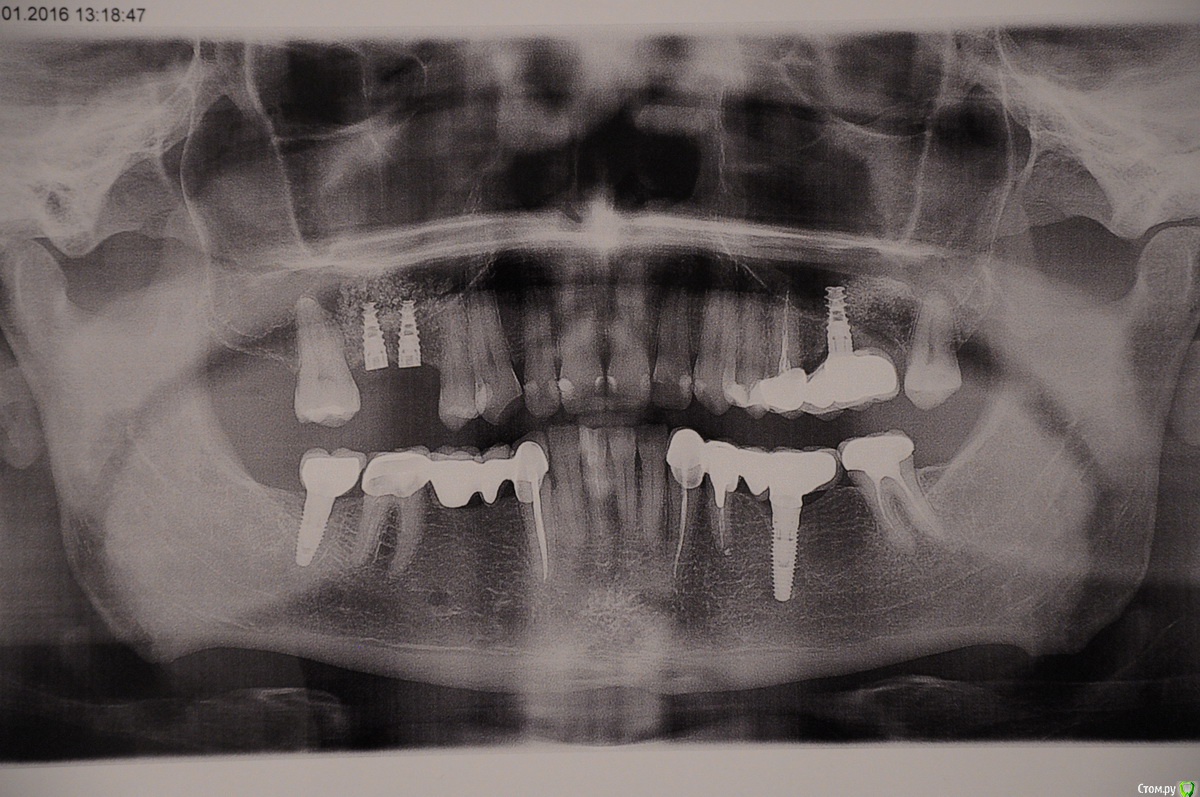

Cursor Опубликовано 5 февраля, 2016 Поделиться Опубликовано 5 февраля, 2016 Уважаемые доктора, проконсультируйте, пожалуйста на предмет импланта. В июле 2015-го была имплантация на месте 6 и 7 зуба слева вверху (2 имплантата Алфа Био + открытый синус-лифтинг), один имплант не прижился (шатался) было решено его удалить и протезировать на на оставшийся имплант и свой зуб.Поставил коронки, все вроде ничего, но при жевании есть тупая боль на месте импланта. У меня есть подозрения, что он похоже тоже не особо прижился? Можете проконсультировать, что лучше сделать: выкрутить или дать ему шанс укрепиться и боль со временем пройдет? Панорамный снимок прилагаю. P.S. Справа вверху тоже установил два импланта на днях, но уже у другого доктора. Ссылка на комментарий